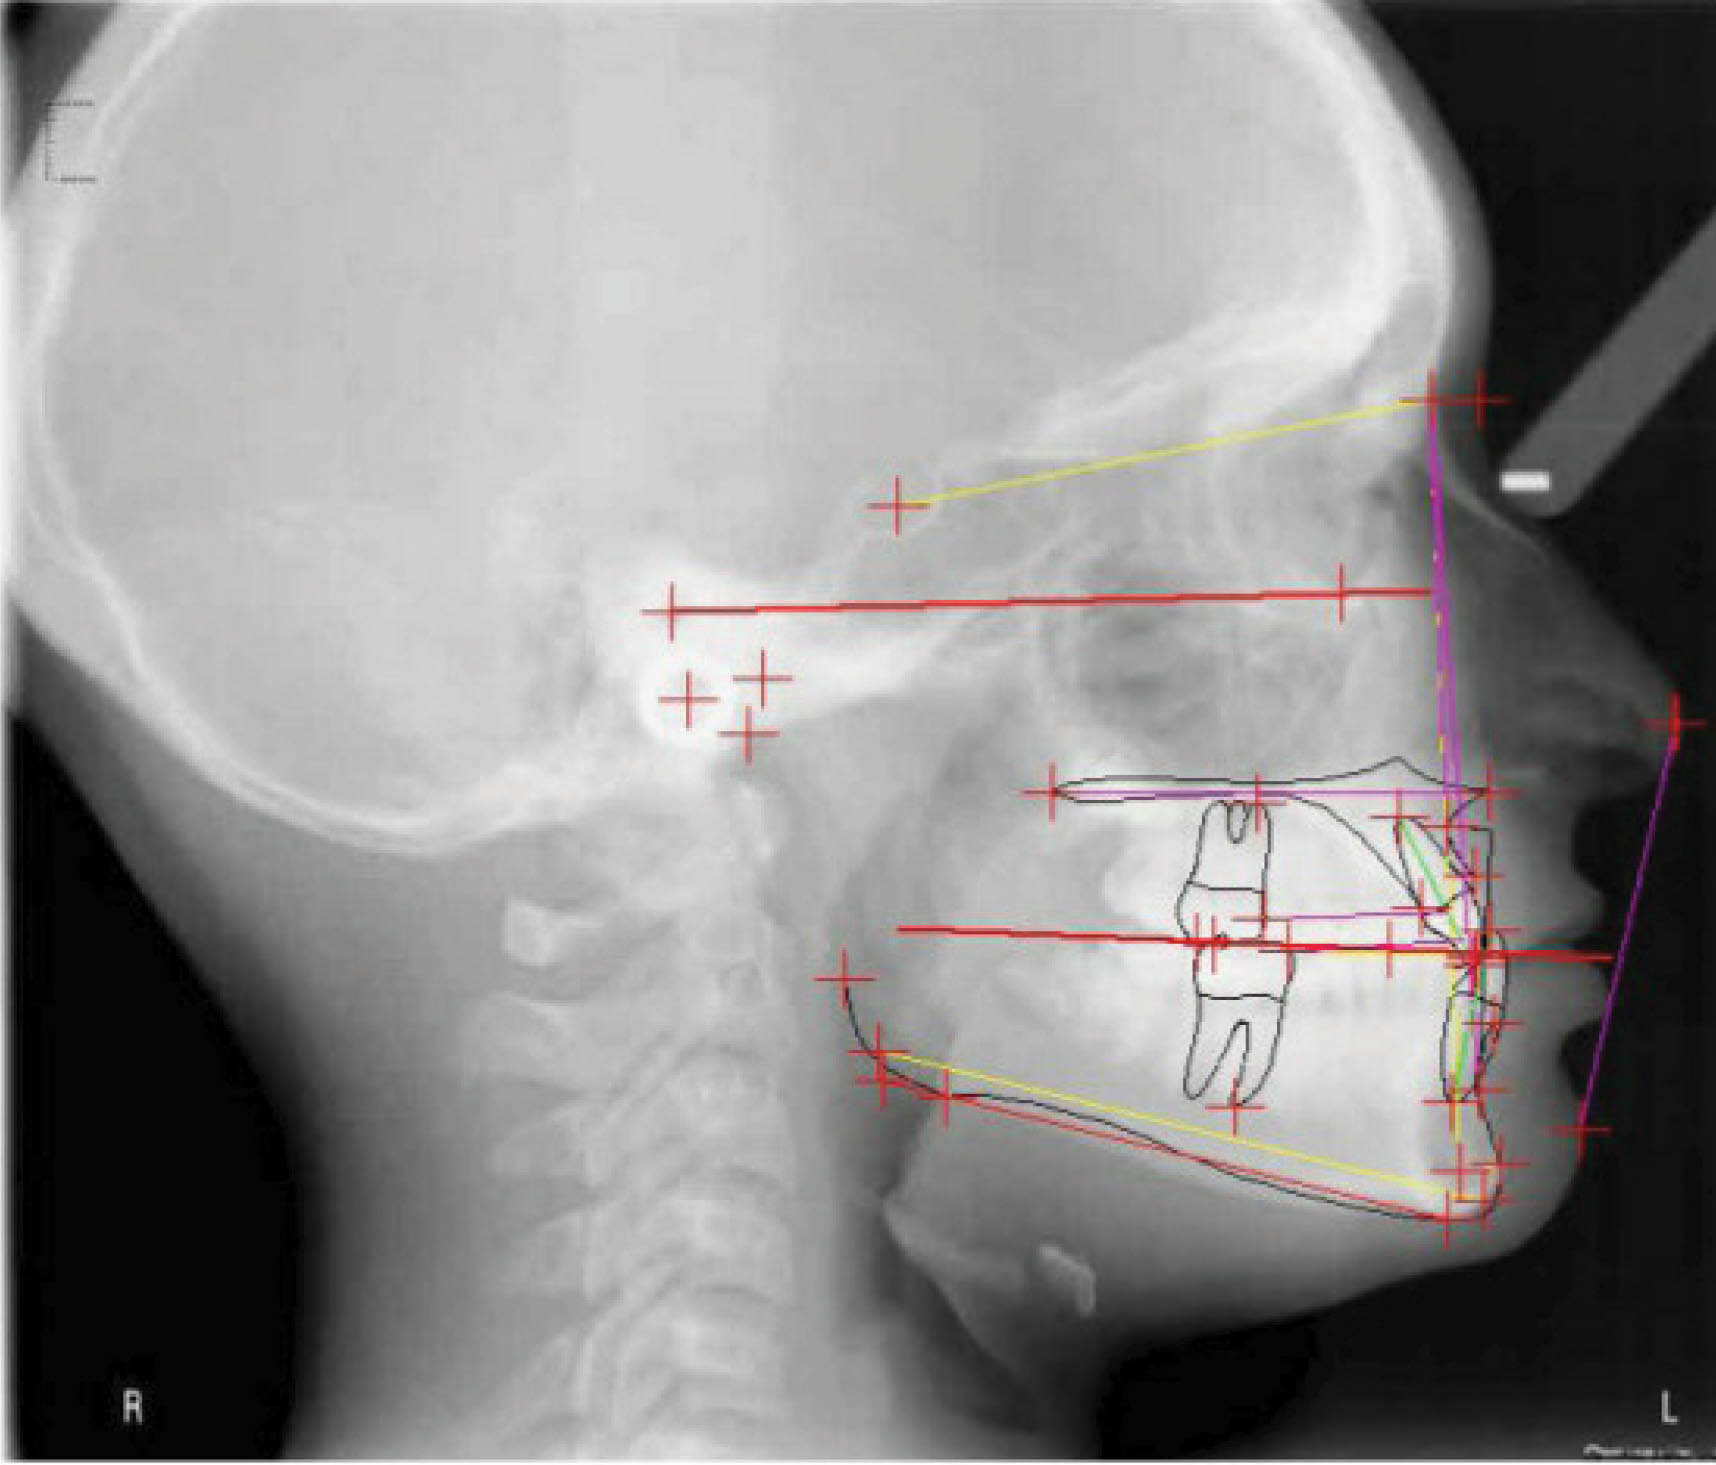

بیمار بعدی یک دختر ۱۲ ساله با اکلوژن ClII/1 و دیپ بایت است. فضا بین قدامیهای بالا و کرادینگ قدام پایین مشخص است. عکس OPG طبیعی است. لترال سفالومتری نشان دهنده رابطه کلاسII فکی و افزایش جزئی در ارتفاع صورت است (شکلهای 98-۶ الی 100-۶). به میزان زیاد لثه در زمان لبخند دقت کنید. چک لیست او به شرح زیر است:

شکل 98-6

شکل 99-6

شکل 100-6

الاستیک کلاسII برای این کودک در حال رشد تجویز گردید. برای کاهش میزان لثه در گامی اسمایل اینتروژن مطلق سانترالهای بالا در نظر گرفته شده است. برای اصلاح کرو اسپی، اینتروژن قدام پایین هم انجام شد. اکستروژن خلف برای اصلاح دیپ بایت صحیح نمیباشد چون ارتفاع عمودی صورت کمی بیشتر از نرمال است.

در عکسهای پایان کار (شکلهای 101-۶ الی 103-۶) اصلاح اکلوژن کلاسII، اوربایت و اورجت طبیعی، و دندانهای مرتب مشخص هستند. مقایسه تصاویر قبل و بعد (شکلهای 104-۶ و 105-۶) نشاندهنده کم شدن گامی اسمایل بیمار است که خود شاهدی بر اینتروژن مطلق انسیزورهای بالا میباشد. عکس نهایی OPG طبیعی است و سوپر ایمپوز نمودن عکسهای لترال سفالومتری نشاندهنده ثابت ماندن موقعیت ۶ بالا و کنترل خوب روی پلن مندیبل است.

نتیجه: درمان ۲۸ ماه به طول انجامید، و ۲ قالبگیری مجدد داشتیم و از الاستیک کلاسII ۲ انسی استفاده شد.